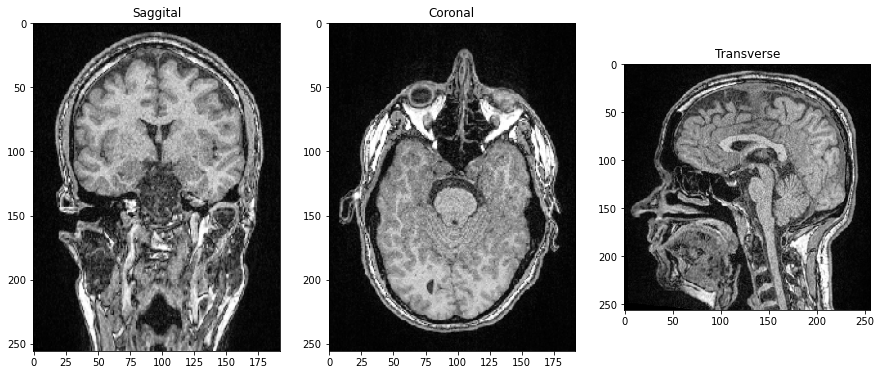

Como las tres dimensiones son dimensiones espaciales, también podemos hacer cortes ortogonales al plano de la imagen y correspondientes a los Planos Anatómicos. Para orientar las imágenes correctamente, podemos transponer sus ejes agregando .T al final.

saggital = image_stack[:,:,128].T

coronal = image_stack[:,128,:].T

transverse = image_stack[96]

fig, axs = plt.subplots(1, 3, figsize=(15,15))

# show orthogonal planes

axs[0].imshow(saggital, cmap='Greys_r')

axs[0].set_title('Sagital')

axs[1].imshow(coronal, cmap='Greys_r')

axs[1].set_title('Coronal')

axs[2].imshow(transverse, cmap='Greys_r')

axs[2].set_title('Transversal');